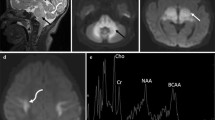

In MRS investigations, the ratios of NAA/Cr and Cho/Cr in 14 cases were found to be 1.31 ± 0.17 and 1.04 ± 0.27, respectively (Fig. 4). Lactate peak was not found in any of the cases.

At follow-up treatment, four of our patients had only brain MRI and one of the patients had brain MRS. Control MRIs were performed after an average of 72 days (59–90 days). While no changes in findings were determined in one case, a decrease in the subarachnoid distance in another case and an increase in the thickness of the corpus callosum in a separate case (Fig. 5) were found. Before and after treatment MRI of the last case were normal. After treatment, increases in the ratios of NAA/Cr and Cho/Cr were determined in the case who had control MRS investigations (ratios of before and after treatments: 1.01, 0.85, and 1.39, 0.96, respectively; Fig. 6).

Pre-treatment magnetic resonance (MR) spectroscopy performed left basal ganglia that shows brain atrophy on MR imaging and on MR-spectroscopy the NAA/Cr ratio: 1.01, the Cho/Cr ratio: 0.85 (a). Post-treatment MR spectroscopy image shows the increased NAA/Cr and Cho/Cr ratios in the same area (1.39 and 0.96, respectively) and decreased atrophy (b)

MR spectroscopy is a noninvasive technique that has gained wide clinical use and has been found beneficial in the assessment of neuronal function and metabolite incompatibilities in the brain [10]. The PRESS sequence with TE performed in all cases had a maximum signal/noise ratio. We were specifically interested in assessment of NAA/Cr and Cho/Cr ratios. NAA, which is present in neuronal cells, is considered to be a marker for neuronal development. Therefore, it was identified as a neuronal determinant. Neuronal damage or loss will result in decreased NAA levels [9]. Cho, which is a membrane component, has been used to infer information about myelination and cell membrane turnover. In infants, the Cho/Cr ratio is higher than that of adults. The Cho/Cr ratio declines rapidly from age 1 month to 1 year, then declines more slowly until an age of 2 years [18]. Because choline is present in the structure of myelin-associated macromolecules, increased myelination leads to a decrease in Cho/Cr ratio [10]. The ratios of NAA/Cr and Cho/Cr were found to be 1.31 ± 0.18 and 1.05 ± 0.29 in our study. Our study is a retrospective study with no control group. The changes to be determined in Cho peak used to evaluate myelination may be helpful in clarifying the pathogenesis of abnormalities occurring in vitamin B12 deficiency. The increases in the ratio of NAA/Cr after treatment in a case with control MRS in our study group may be physiological changes or it can also support the increased number of neurons as response to therapy. Increases in the ratio of Cho/Cr may support the acceleration in myelination. Nevertheless, it is required that these results should be shown in more number of patients.

The MRS study is limited in cases with vitamin B12 deficiency, therefore we could only find two studies in the literature [11, 17]. In one case study of a 6-month-old infant with nutritional vitamin B12 deficiency, MRS of the white and gray matter of the brain revealed an accumulation of lactate and a sustained depletion of choline-containing compounds, reflecting a disturbance of oxidative energy metabolism in brain cells. This could be due to an increase in anaerobic glycolysis. In our recent study, differently, voxel was located at the basal ganglia in all cases. Pathological signal changes in the basal ganglia with MRI were not determined in any of our cases. Although increased diffuse signal was found around periventricular white matter in one case, abnormal lactate peak was not determined with MRS investigation in any of the cases. This finding does not support the study of Horstmann et al. [11]. In our patients, due to absence of a cystic cavity lesions, lactate peak may not be detected. Lam WWM et al. reported that decreased concentration of NAA in MRS [17].